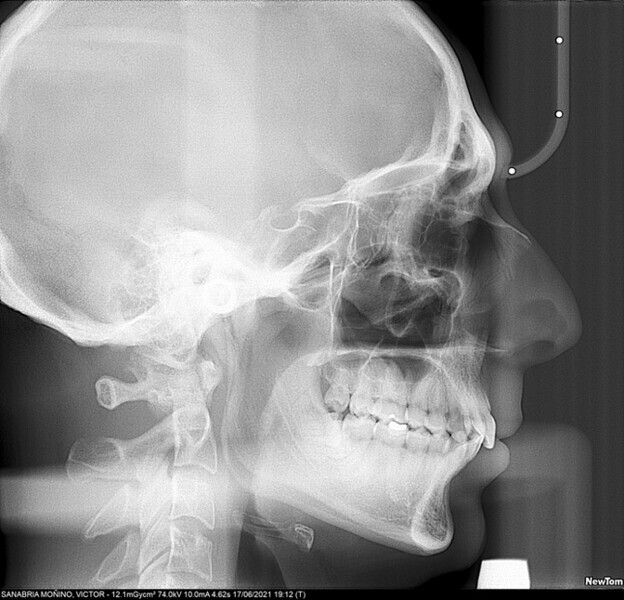

Upon intra-oral examination, all the permanent teeth were visible, except for the mandibular third molars. The molar relationship was a complete Class II, in both arches, and the canine relationship was also Class II, for both the right and left sides. There was mild crowding in both arches, tooth #34 being in linguoversion. The overbite covered more than two-thirds of the surface of the mandibular incisors. A most notable feature was an excessive overjet of approximately 11 mm (Fig. 2).

Figs. 2a–e: Initial intra-oral photographs.